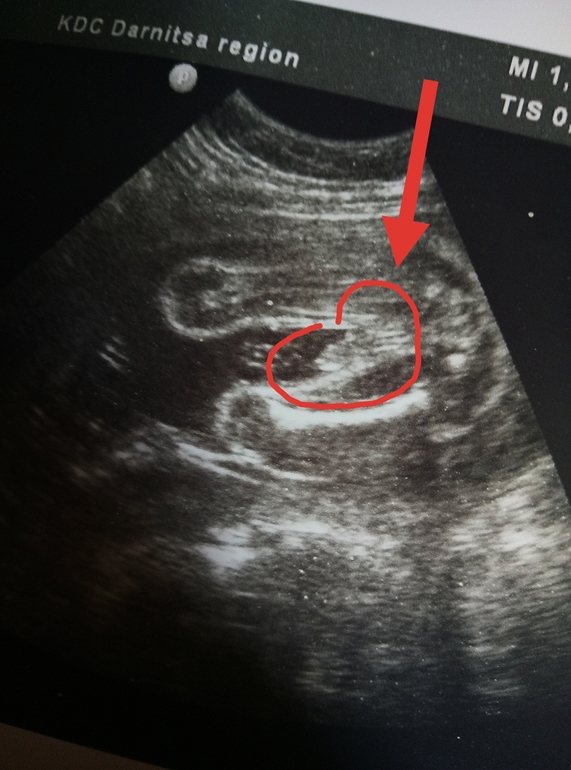

у нас мальчик😍

была сегодня на УЗИ, сказали 100% мальчик,муж сказал"Роберт"

В голове не укладывается...у меня сыночек))